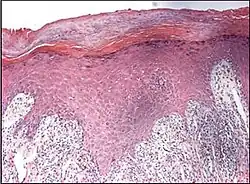

Psoriaform dermatitis typically displays:[2]

- Regular epidermal hyperplasia, elongation of the rete ridges, hyperkeratosis, and parakeratosis.

- Usually:A superficial perivascular inflammatory infiltrate

- Often: Thinning of epidermal cells overlying the tips of dermal papillae (suprapapillary plates), and dilated, tortuous blood vessels within these papillae